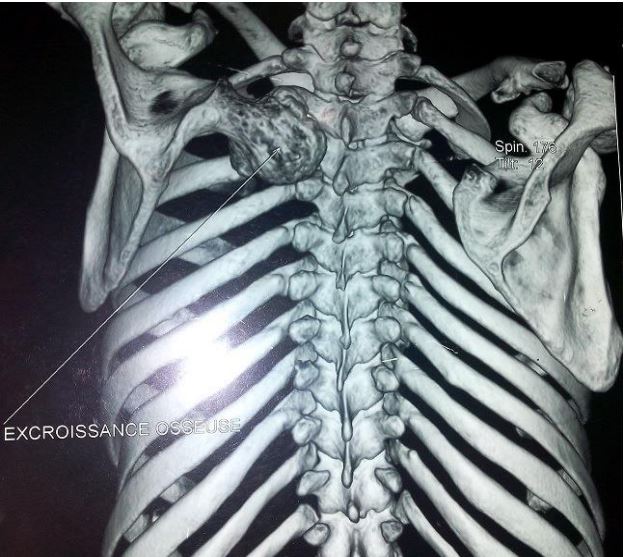

A 24-year-old young man was presented for consultation for a mass on the dorsal side of the scapula that had been present for 3 years. This mass was hard, non-painful and slightly mobile; the scapula formed a voluminous dorsal hump 12 cm long, 8 cm wide and 5 cm thick (Figure 1). This mass led to fatigability of the shoulder during exercise, a limitation of particularly active shoulder joint movements and great aesthetic discomfort. The standard front x-ray of the scapula revealed heterogeneous bone formation at the spinal edge of the scapula (Figure 2). A CT scan confirmed the presence of the large exostosis, the boundaries of which appear regular and corticalized (Figure 3). The patient underwent surgery, with en bloc resection of the tumor and extraction of the detached fragments (Figure 4). The pathological examination concluded that it was an osteochondroma.

Figure 3: Scannographic appearance of osteochondroma of the scapula.